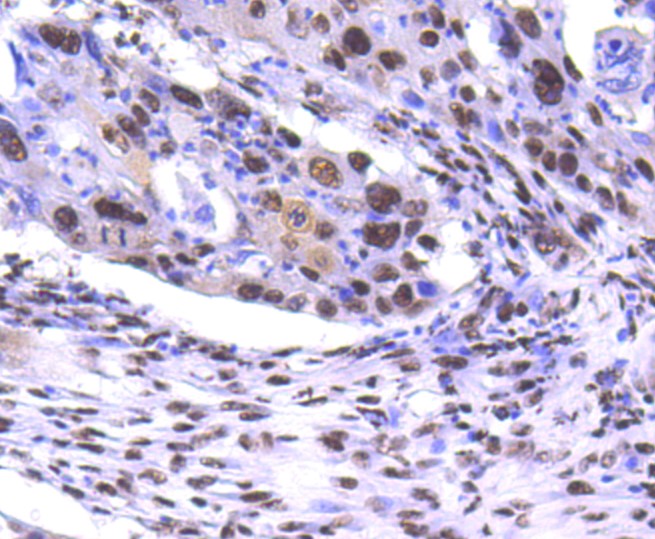

PRP19 (7H10) Monoclonal Antibody

• IHC-P

• IHC

IHC-P 1:200-400

IHC